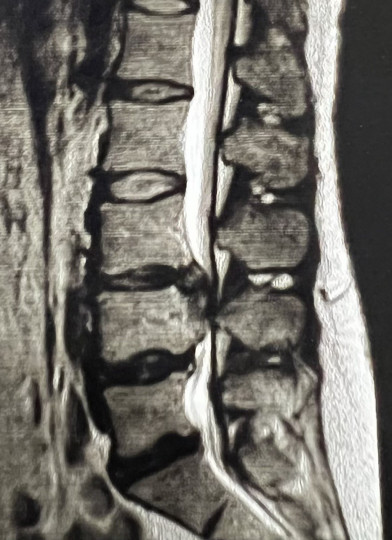

Грижа диску оперувати чи лікувати?

Грижа диску - одне із дуже частих захворювань у людей, і постійно у людей виникає запитання оперувати чи лікувати, постараюсь коротко і доступно описати проблему:

⁃ розмір грижі диску впливає на призначення показів до операції, але не завжди - покази визначає лікар нейрохірург при неврологічному огляді. Іноді грижа диску в поперековому відділі хребта буває розміром 1см, вона медіанна (стоїть по середині), хребтовий канал широкий і корінцеві болі відсутні (відсутня біль в ногах) - таку грижу оперувати непотрібно, а буває грижа диску 6 мм, хребтовий канал вузький і виражена біль в нозі - таку грижу потрібно оперувати;